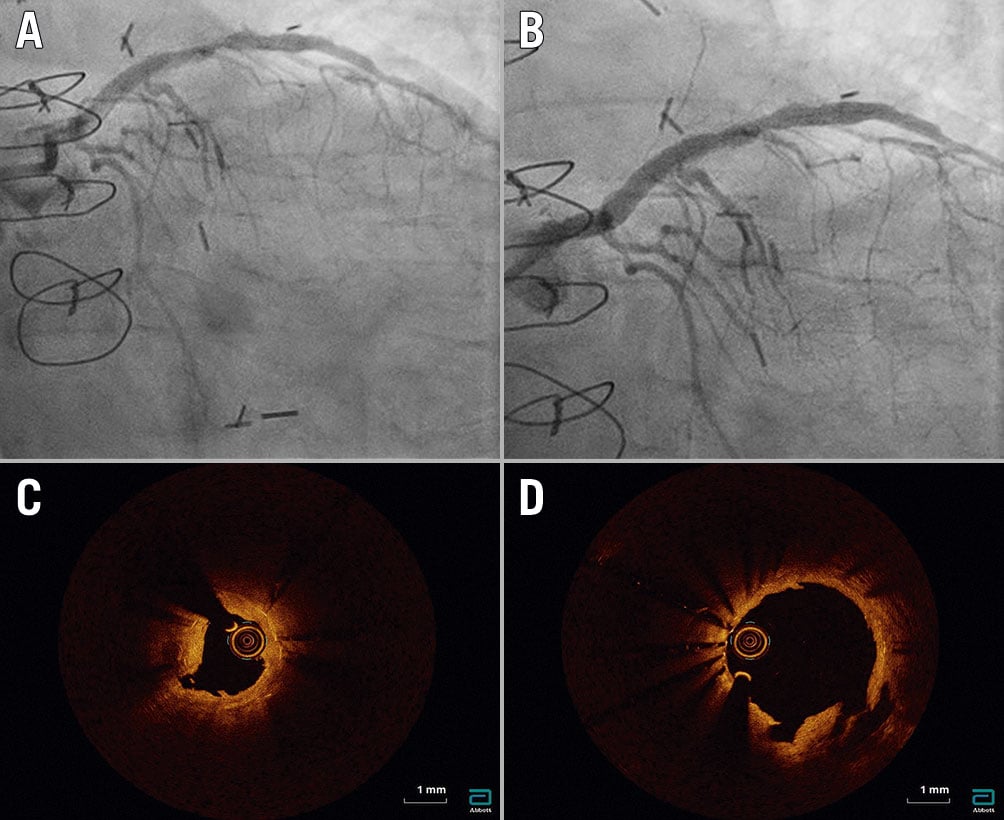

In the three patients for whom OCT data were available pre- and post-PCI, the mean MLA increased from 2.75±0.88 mm2 to 5.49±1.23 mm2 due to an increase in the mean MSA from 3.73±0.58 mm2 to 6.38±0.77mm2 and a decrease in the mean neointimal hyperplasia cross-sectional area from 0.98±0.31 mm2 to 0.89±0.77 mm2 (Table 4). Adequate stent expansion and multiple peri-stent calcium fractures were observed post-PCI (Figure 3, Figure 4).

Figure 3. Lesion 23. A) Pre-percutaneous coronary intervention (PCI) angiogram showing severe in-stent restenosis (ISR) in the left anterior descending artery. B) Post-PCI angiogram showing mild residual stenosis. C) Pre-PCI optical coherence tomography (OCT) showing ISR and stent underexpansion (minimum stent area [MSA] 3.42 mm2) due to peri-stent calcium. D) Post-PCI OCT showing adequate stent expansion (MSA 5.62 mm2), a reduction in neointimal tissue and multiple peri-stent calcium fractures.